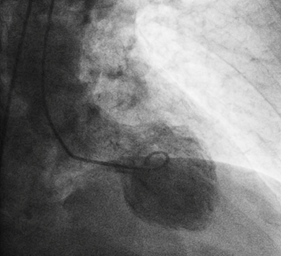

A 81year old gentleman presented to the emergency department accompanied by emergency physician and paramedics with typical angina symptoms for last 1hour associated with Dyspnoe, nausea  and vomitimg. The chest pain has subsided with administration of Morphin i.v. On arrival in the emergency department, one immediate 12-lead ECG  was done, that showed lateral wall  ST-elevated myocardial infarction (Figure 1). Wihout delay as per the current guidelines one emergency  angiogram was done, that revealed one occluded Ramus diagonalis branch of Left anterior descending artery(Figure-2) and one Plaque rupture in mid segment of right coronary artery with subtotal occlusion (Figures 2 & 3). Immidiately the coronary flow in Ramus diagonalis -2 was regained and the culprit lesion was treated with 2 drug eluting stents  2,25X14mm size, the end result was TIMI III Flow in Ramus diagonalis -2. During the procedure the EKG showed ST elevation in lead II, III and aVF with intermittent Atrioventricular Block III, Blood pressure was 100/56mm Hg and heart rate was 65 per minute. We decided to perform the angioplasty of Right coronary artery. The flow in right coronary artery was restored and the culprit lesion as treated with 2 Drug eluting stents 3.0X19 mm and 3,5X 14mm, resulting in TIMI III Flow. The ST elevation leads II, III and aVF were settled.

Figure 3 Coronaryangiography.